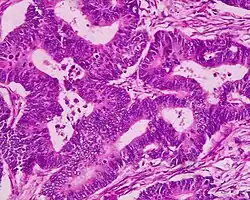

Als Adenokarzinom bezeichnet man einen bösartigen (malignen) von der Deckzellschicht (Epithel) ausgehenden Tumor, der aus Drüsengewebe hervorgegangen ist. Die gutartige (benigne) Zellveränderung von Drüsengewebe nennt man dagegen Adenom.

Adenokarzinome kommen vor allem im Bereich der Verdauungsorgane, Lunge, Niere und Genitalorgane vor. Die Therapie richtet sich nach dem Ursprung des Tumors (Primärtumor) und der Ausbreitung (TNM-Stadium). Mikroskopisch spielt der Differenzierungsgrad (Ähnlichkeit mit dem Normalgewebe) eine große Rolle, welcher als „Grading“ in das TNM einfließt.

Adenokarzinome lassen sich im Rahmen der pathologischen Aufarbeitung aufgrund ihrer Gestalt (Morphologie), ggf. Schleimsekretion (Muzingehalt) und Proteinausstattung typisieren sowie teilweise auch dem Ursprungsorgan zuordnen, was insbesondere bei Metastasen wichtig ist, um den Ausgangstumor (Primärtumor) aufzuspüren (vgl. CUP-Syndrom). Zusammengefasst:

- Morphologisch besser differenzierte Adenokarzinome zeigen ein „drüsiges“ Wachstum, z. B. in Röhren (tubulär, azinär, duktal) oder siebförmig (kribriform). Andere Wuchsformen sind z. B. papillär (fingerförmig) und mikropapillär (knospenartig).

- Schlechter differenzierte Adenokarzinome wachsen oft „am Stück“ (solide) oder einzelzellig (diffus) und können ggf. nur mittels Zusatzuntersuchungen von anderen Karzinomen wie z. B. einem schlecht differenzierten Plattenepithelkarzinom unterschieden werden. Mischform: adenosquamöses Karzinom.